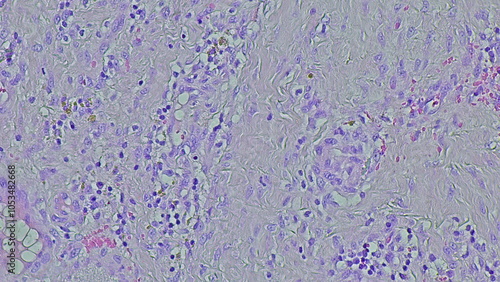

Mikrofotografi - Plakater, Poster, Billeder på lærred